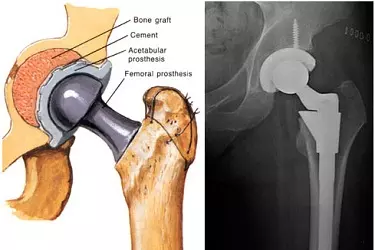

Once your pre anesthesia check up is done you will be admitted in the hospital one day prior to the surgery date. Revision total hip replacement is a more complex procedure and takes longer to perform than primary total hip replacement. Your surgeon will remove the previous implant very carefully to preserve as much bone as possible and will replace it with the specialized revision hip implants and will test the motion of the joint to ensure the implants are well-fixed and that the ball is stable inside the socket. After surgery, you will be moved to the recovery room, where you will remain for several hours while your recovery from anesthesia is monitored.